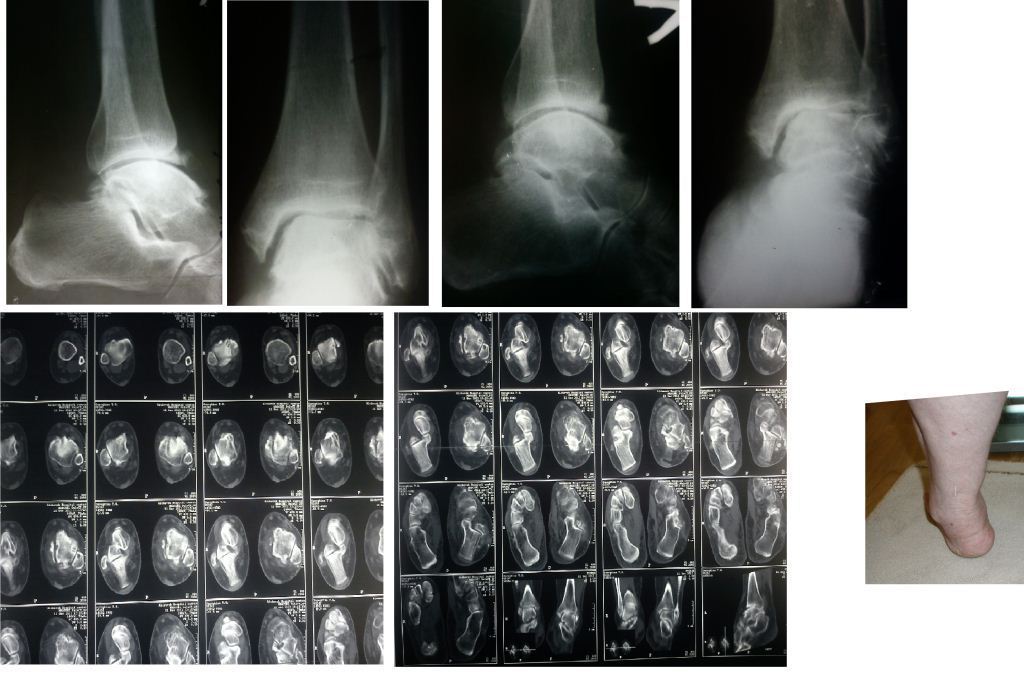

Уважаемые коллеги. Пациентка 1948 г.р., беспокоят боли в области левого

голеностопа, прогрессирующая деформация(варусная) и неустойчивость

сустава.Травму отрицает. Болеет более 5-ти лет. Согласна на операцию.

Вопрос об артродезе г/ст сразу не вызывал сомнений. Но, если это

артропатия, то насколько велик риск несращения? Помогите определиться с

диагнозом и сответственно с тактикой. Невролог патологии не находит. Во

вложенных файлах рентгенограммы за 2007 и 2012 гг.? фото и КТ свежая.